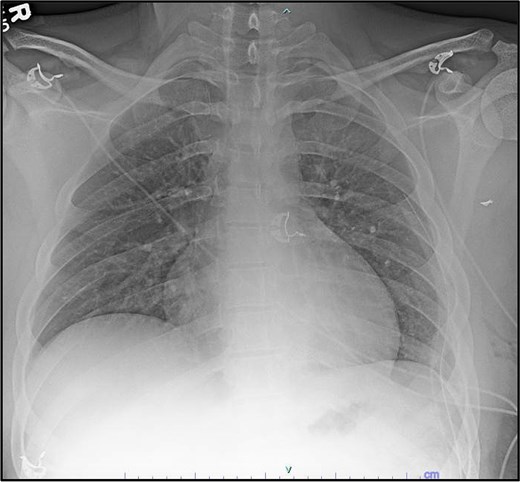

Trauma workup imaging began with a chest X-ray (CXR), triggering a chest CT given the bullet’s location in the mediastinum. With the bullet near the great vessels, a transthoracic echocardiography (TTE) and a CT using a cardiac gated/dissection protocol were obtained. The visualization of vasculature and normal anatomy was limited by metallic artifact from the foreign body (Fig. 1). The chest CT demonstrated the largest bullet fragment located in the region of the aortopulmonary window, with no measurable distance between the bullet fragment and inferomedial margin of the aortic arch (Fig. 2). Less than 2 mm of separation was visualized between the bullet and the superior aspect of the left main pulmonary artery (Fig. 2). There was no contrast extravasation from the vasculature to suggest active bleeding, and there was no obvious mediastinal fluid collection / hematoma. TTE also visualized the aortic arch and showed no clear injury with laminar flow across the aorta. His initial CXR demonstrated a normal cardio-mediastinal silhouette (Fig. 1a). A small pneumothorax was seen with 2 mm pleural separation but repeat CXR did not indicate expansion, so chest tube placement was deferred (Fig. 1a and b). Upper extremity imaging suggested soft tissue laceration and bullet trajectory without arterial damage.

Preoperative imaging indicating the location of the projectile and image obstruction by metal artifact: Initial CXR (a), day 2 CXR (b).